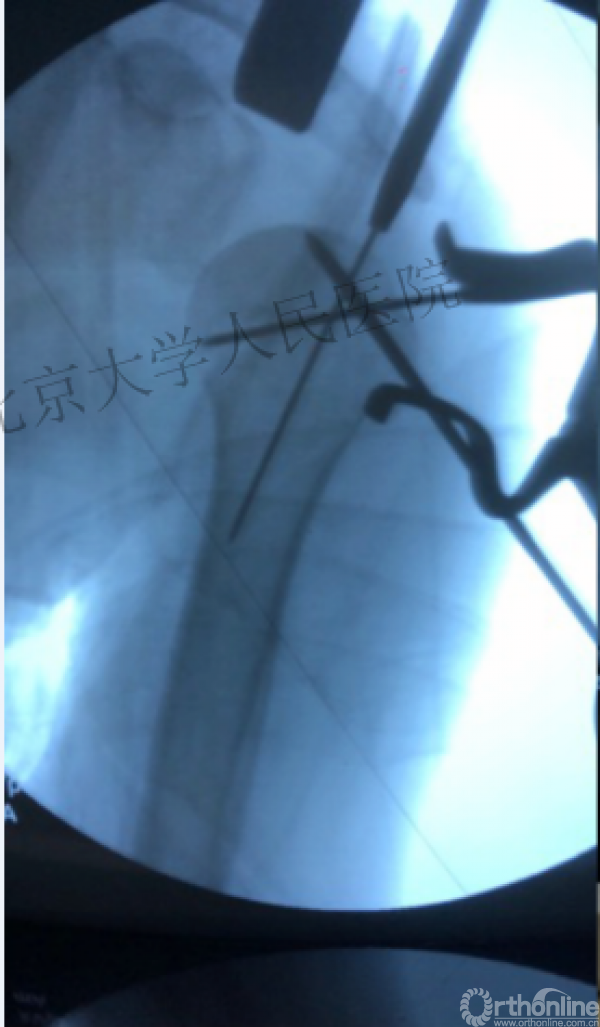

术中片

可否有更好的进钉和复位的更好帮助办法?

进钉更完美——我们的帮助